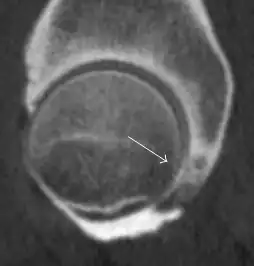

Synovial chondromatosis can be confidently diagnosed by X-ray when calcified cartilaginous chondromas are seen. However, other synovial proliferative processes, such as pigmented villonodular synovitis, require MRI for accurate diagnosis, although noncalcified synovitis can be suspected in radiographs by indirect signs, such as soft tissue swelling and/or erosions in the femoral head, femoral neck, or acetabulum (Figure 7).[1]

Figure 7:

Axial CT image of pigmented villonodular synovitis eroding the posterior cortex of the femoral neck.[1]

Sagittal T2* gradient echo image showing a posterior soft tissue mass with hypointense areas secondary to hemosiderin deposition.[1]

In synovial proliferative disorders, MRI demonstrates synovial hypertrophy. In the case of PVNS, characteristic foci of low signal intensity related to hemosiderin deposition are better seen on gradient echo T2* images (Figure 7). In the case of synovial osteochondromatosis, the synovial hypertrophy is accompanied by intermediate signal cartilaginous loose bodies and/or low signal calcified loose bodies.[1]